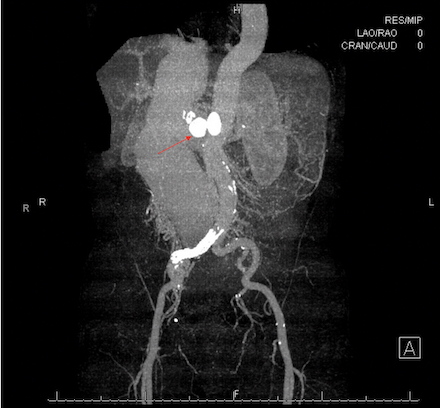

Abdominal computed tomography venogram showed dilation of the IVC up to 8cm and an aortocaval fistula at the level of the right renal vessels, resulting in an atrophic right kidney. Cardiac catheterization was notable for a cardiac output (CO) of 12L/min, cardiac index (CI) of 7L/min/m2 and reduced systemic vascular resistance (SVR). He was managed with beta blockers and diuretics, followed by TEE-guided cardioversion for atrial flutter to restore sinus rhythm. Vascular surgery performed a successful, first of its kind endovascular repair of the abdominal aorta with stenting of the right common iliac artery and placement of a 20mm Amplatzer Septal Occluder device in the right renal artery. He tolerated the procedure well, and post-operative TTE showed a recovered LVEF of 55-60% and CO of 6L/min.